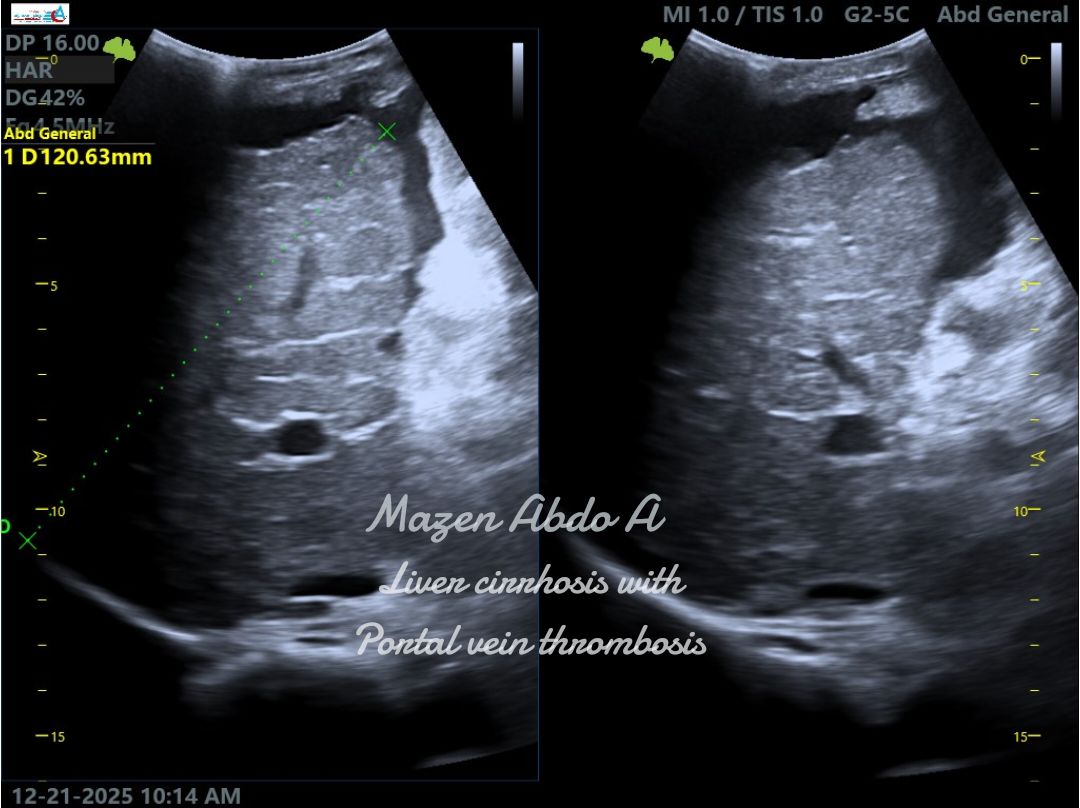

“Ultrasound cases from my daily practice

Liver Cirrhosis with Portal Vein Thrombosis (PVT)

Portal vein thrombosis is a serious complication of liver cirrhosis. On ultrasound, it may appear as echogenic material within the portal vein with absent or reduced Doppler flow. Chronic PVT can lead to portal hypertension, splenomegaly, and the development of collateral vessels. Early detection by Doppler ultrasound is essential for timely management and to reduce complications.”